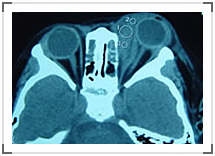

眼眶非特异性炎症并非由细菌或病毒感染导致,而是一种免疫性炎症反应。因其形成肿瘤样包块,而镜下为慢性炎症改变,故名“炎性假瘤”。临床表现包括炎症红肿热痛和肿瘤占位效应。炎症类型多样,可单独累及眼外肌或泪腺,可形成局限性肿块,也可弥漫于眶内。CT表现为眼外肌肥厚、泪腺肿大、眶内不规则肿块或弥漫性高密度影。活动期炎症首选皮质类固醇治疗,可口服、局部注射或静脉滴注。放射治疗也有一定效果。药物不敏感者选择手术治疗,由于病变边界不清,很难切除完全。该病易复发,迁延不愈。(如图,泪腺炎)